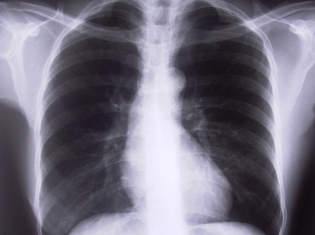

(RxWiki News) Combating inflammation is an important step in treating Chronic Obstructive Pulmonary Disease (COPD). Sometimes a drug is successful but like anything, there are risks.

Using extra-fine inhaled corticosteroids, Beclomethasone Oral Inhalation (BOI) marketed as Qvar, Beclovent and Vanceril, or oral corticosteroids, did not aid in reducing nitric oxide in the lungs.

Despite its ability to penetrate into the small airways of the lungs, oral corticosteroids may not effective in reducing small airway inflammation in COPD patients.